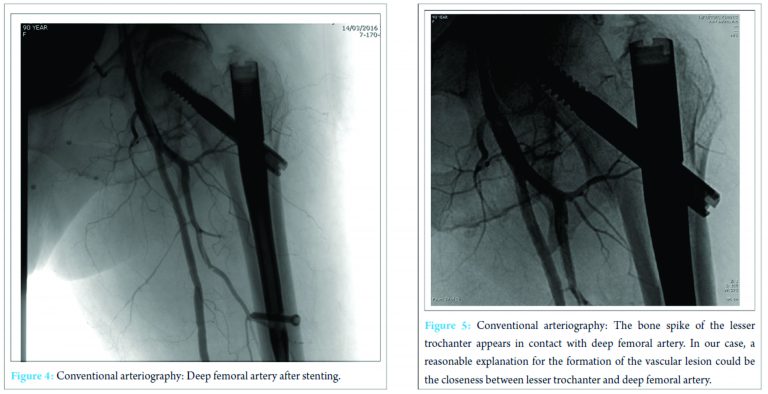

Therefore, a stent was placed (Fig. 4). After this procedure, the clinical conditions improved and the patient was discharged 4 days later with stable blood exams. On the last clinical control, 3 months after the stenting, the patient was feeling well and had started physical rehabilitation.

Hip fractures in older patients are the most common fractures treated by orthopedic surgeons. The incidence increases with age and degree of osteoporosis. The most frequent traumatic mechanism is a low energy fall from a standing height [5]. Proximal femoral fractures may be treated using different techniques of fixation. Screws or partial arthroplasty proves to be efficient for the synthesis of intracapsular fractures, whereas nails and plates are the most commonly employed for extracapsular fractures. In our case, we treated a 31-A2 fracture with a gamma nail. The role of intramedullary fixation for the treatment of this kind of fracture is still debated. Anyway, gamma nail is often preferred to slide hip screws, especially, because of easy handling instrumentarium and implant versatility. According to many authors, gamma nail has proved to be a safe and efficient fixation of pertrochanteric fractures [6]. Vascular complications after intramedullary fixation of pertrochanteric fracture are rare. These complications can develop after fracture during intramedullary hip nailing and displacing of bone fragment during fracture or repair. Furthermore, some authors suggest that manipulation of atherosclerotic vessels of the leg on the fracture table may injure their brittle endothelium with an increased risk of bleeding and thromboembolic events. Vascular injuries may be hemorrhagic or thrombotic, acute (hemorrhage), or delayed (pseudoaneurysm formation). Regardless of the type of vascular lesion, the most frequently injured vessel is the deep femoral artery followed by its perforating branches [4]. False aneurysms or pseudoaneurysms are surrounded by a thin fibrous capsule in contrast to true aneurysms that consist of the true layers of the arterial wall. The fibrin capsule is made of soft tissues and/or hematoma adjacent the vessel. There is a high risk of enlargement and rapture of the vessel, in particular, when the dimension of the pseudoaneurysm is superior to 3 cm. Rapid expansion, infection, skin or soft tissue necrosis, neuropathy, distal ischemia, pain, or rupture are the most important indications for repair [7]. The incidence of pseudoaneurysm after hip fracture is very low (0.21% of incidence) and rarely reported as a consequence of dislocated bone fragments. According to literature, arterial damages can occur because of bone spikes, tip of the screws, drills, displaced implants, and retraction of surrounding tissue [8]. In our report, X-ray imaging after surgery shows the proximal migration of lesser trochanteric fragment, due to the action of iliopsoas that fits on the lesser trochanter, near the pseudoaneurysm. According to symptoms and instrumental studies, it seems that dislocated fragment may have damaged the deep femoral artery that lies near proximal femur (Fig. 5). However, in almost 25% of pertrochanteric fracture, the lesser trochanter was involved, but vascular complications rarely occur, probably thanks to vessels elasticity. Clinical manifestations of a false aneurysm after hip fracture have been reported between 3 days and 14 years, but in cases of dislocated lesser trochanter being responsible for vascular lesion, these manifestations are more frequent between 18 and 36 days. Probably clinical appearance of the pseudoaneurysm is delayed until the patient starts mobilization that can dislocate bone fragments. In this case, we found the pseudoaneurysm 16 days after surgery, below the average reported in literature. Often it is difficult to identify this complication because of non-specific symptoms including pain, edema, and swelling that are common after hip surgery. We should suspect a pseudoaneurysm if the patient presents falling of hemoglobin level, pulsatile swelling, or venous engorgement, and we can diagnose this complication by duplex ultrasound (US), conventional angiography, and computed tomography (CT) angiography [9]. US is the method of choice for diagnosis of pseudoaneurysm with sensitivity between 94 and 97%. As in our case, conventional angiography (or CT-angiography) can be useful to confirm and to better define the vascular lesion. There are numerous treatment options for deep femoral artery pseudoaneurysm: Conservative management for smaller aneurysms, US-guided compression, percutaneous US-guided thrombin injection, percutaneous US-guided collagen injection, insertion of coils, covered stents, and open surgery [10]. The treatment we chose consisted in positioning an endovascular stent covered by polytetrafluoroethylene. After the procedure, symptoms improved and the patient was able to resume the rehabilitation program a few days later.